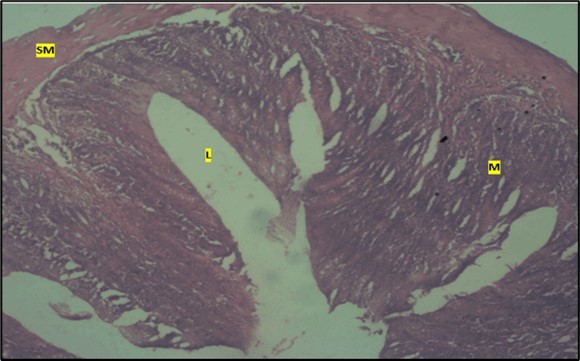

Results from the large intestine histological observation showed normal appearance of epithelial cells lining the mucosa with no pathological observations in control animals (Figure 5). However, administration of Abelmoschus esculentus at low dose showed dysplasia of cells and loss of normal epithelial shape (Figure 6) and the high dose group showed mild dysplasia (Figure 7)

Figure 5.Control showing the lumen (l), the epithelial cells lining the mucosa (m) appearing normal H & E. X40.

Figure 6.Low dose showing the lumen (l), smooth muscle layer (sm) and dysplasia of the mucosa (m). there is loss of epithelial shape H & E. X40.